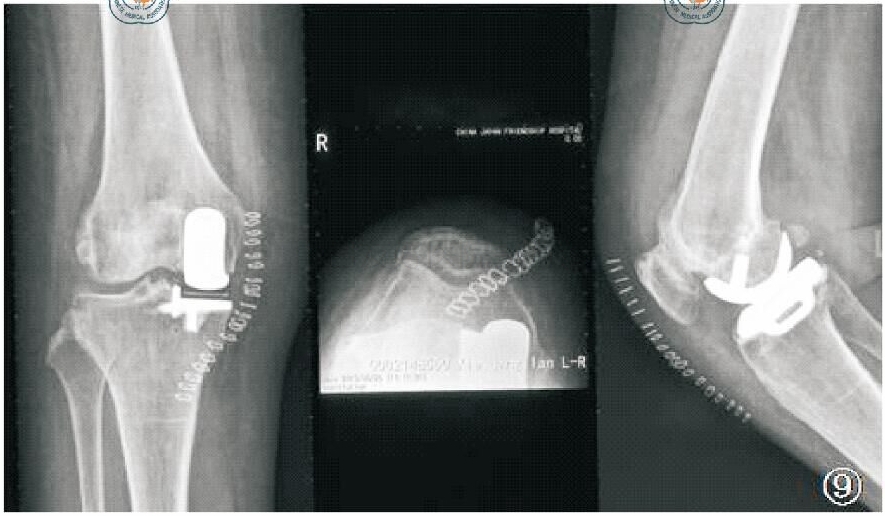

X线片六:术后正位、髌骨轴位、侧位

前后位X线:患者仰卧于 X 线床,双脚并拢,双膝标准正位状,中心线对准髌骨下缘直射入,即以胫骨侧假体关节面为中心照射。侧方X线:患者仰卧于X线床上,屈膝 20°~30°,膝部外侧缘紧靠暗盒,髌骨与暗盒垂直,中心线对准关节线垂直射入,即以股骨部假体为中心。

对于胫骨假体:①在前后位,假体与胫骨轴成角90°(容许5°误差)。其外侧靠近髁间嵴,内侧缘达到胫骨内侧骨皮质,并允许轻度伸出,但不要超出胫骨皮质内侧2 mm。骨—假体界面应该显示出薄层连续骨水泥层并向骨质渗透几毫米。骨水泥在外侧面及龙骨周围渗入的范围比在中间渗入的更深。②在侧位,胫骨假体需要后倾7°,即假体水平面向后下倾斜与胫骨纵轴成7°角(容许5°误差)。假体后缘应该达到后侧皮质,但悬出不超过 2 mm。若悬出过多,可能意味着胫骨假体龙骨槽开槽时损害了胫骨后侧骨皮质。

胫骨假体前后位、侧位示意图

对于股骨假体:①在前后位,假体因为伸直位股骨假体相对于胫骨内旋了15°通常看起来很像一个凹背座椅。在冠状面上,股骨假体中心杆轴线平行于股骨机械轴线,也就是与股骨解剖长轴大约呈7°(容许10°误差),否则股骨假体为内翻或外翻,降低关节面的有效接触面积。②在侧位,假体中央固定柱轴线应该平行于股骨解剖长轴,容许10°以下屈曲及5°以下过伸。

股骨假体前后位、侧位示意图

X线片九:并发症之活动垫片脱位

X线检查可以发现衬垫移位的位置,同时还可能提示造成移位的原因,如骨赘、骨水泥残留、金属假体移位等。